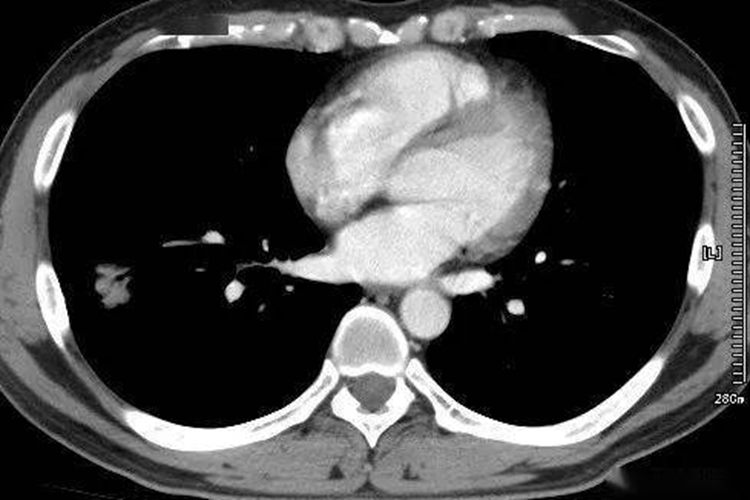

肺癌又称原发性支气管肺癌,临床常见咳嗽、血痰、胸痛、发热等症状。CT检查可见肺内结节或肿块,病灶形态不规则,可呈分叶状。

周围型肺癌:发生在肺段以下支气管,表现为肺内结节或肿块;病灶形态不规则,呈分叶状(分叶征);边缘多发细短毛刺(毛刺征);偏心性空洞,或伴有壁结节;相邻胸膜凹陷,伴线形、喇叭口样索条影牵拉改变;增强扫描呈轻、中度不均匀强化。